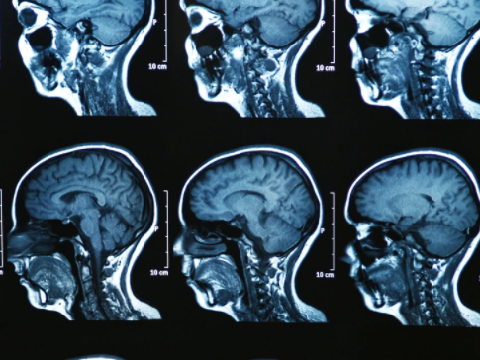

AI xác định ba dạng phụ của bệnh đa xơ cứng trong quét não MRI